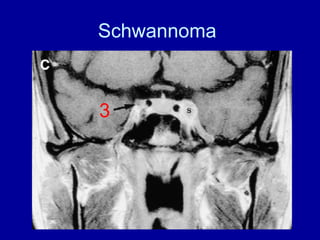

Cavernous segment

Cavernous sinus lesion with 3rd

cranial nerve palsy

Schwannoma

3